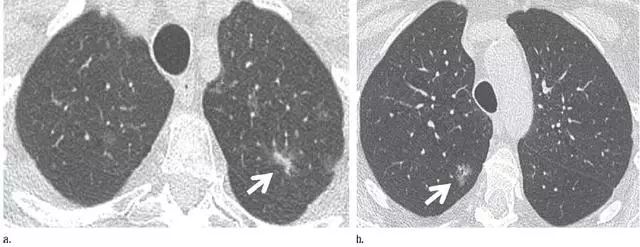

2. 肉芽肿

图 2 CT 图像显示边界清楚的中心钙化(a)或层状钙化(b)结节,均为典型的肉芽肿表现。不建议进一步 CT 随访。